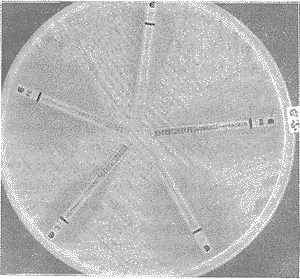

5种常用抗真菌药物对15株不同的真菌的MIC值不同(表1),白念珠菌对KE、IT、FC、AP、FL均敏感,尤以KE及IT最感,MC范围≤0.012~0.5 mg/L(图1),黄曲霉对IT、KE、FC的MIC≤0.125~0.75 mg/L,AP及FL的MIC值>3 mg/L(图2)。结果表明,酮康唑、伊曲康唑具有抗菌谱广,对受试的白念珠菌、黄曲霉、烟曲霉、棕曲霉、米曲霉、卡氏枝孢霉、尖端单孢霉、桔青霉及红色毛癣菌、须癣毛菌、断发毛癣菌等皮肤癣菌均有较好的抑菌作用,氟康唑抗菌谱较窄,仅对白念珠菌、红色毛癣菌、须癣菌敏感,对其它受试的11株菌均耐药。

图1 白色念珠菌药敏图

图2 黄曲霉菌药敏图